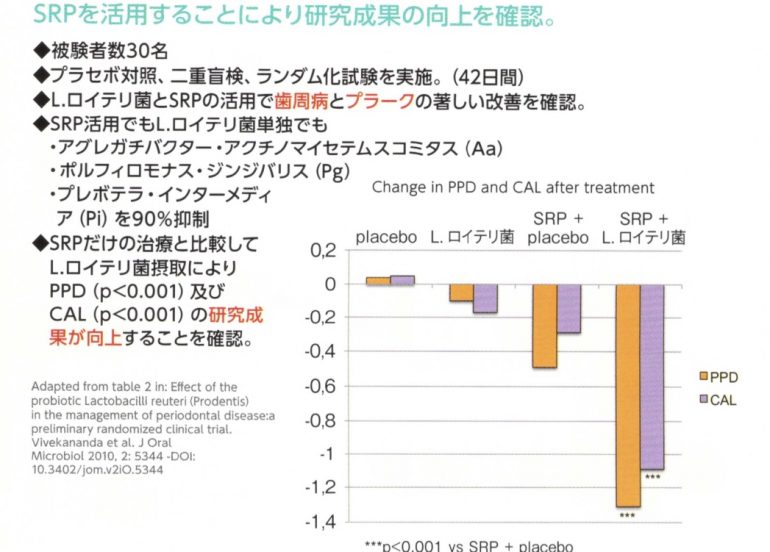

歯周病の原因菌を減少させる

歯周病菌は約90%減少します。歯科医院での専門ケアと組み合わせることで効果があります。